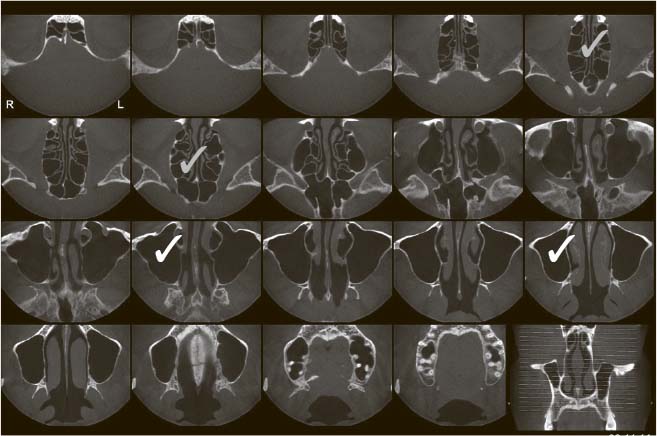

Это рентген 80 lvl. При помощи радиации безболезненно нарезает ваш череп на тоненькие слои (господин Пирогов говорит «Ма-ла-ца!» из мавзолея), по которым можно детально оценить состояние всех структур полости носа, их плотность, характер, взаиморасположение. Незаменимая процедура при хронических риносинуситах: позволяет решить вопрос о необходимости и объеме хирургического лечения. При острых осложненных проблемах дает понять, насколько все плохо.

Компьютерная томограмма придаточных пазух носа, горизонтальная проекция. Белый – верхнечелюстные пазухи, серый – решетчатый лабиринт

Единственное, чего не может КТ, – помочь в диагностике аденоидов. Да, покажет размер. Но не даст объективной картины. Помимо того, у детей ее применение сомнительно по тем же причинам, что и обычной рентгенографии (в случае острой патологии полости носа).